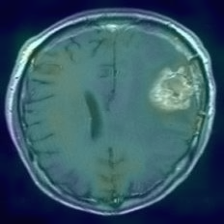

Figure 1: Heatmap Comparison of Unhealthy Images. Different columns show unhealthy MRI images of different positions, sizes, and textures. The first row is the raw image. The second row is the heatmap predicted with PatchCore. The third raw is the heatmap predicted with the proposed method.